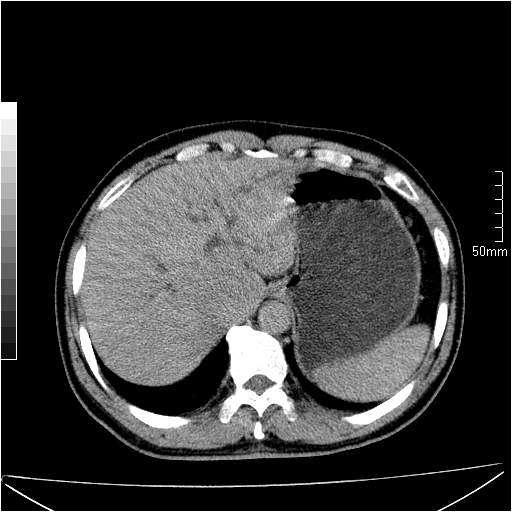

男性,54岁,皮肤黄染,搔痒一周余.b超示肝左叶回声异常.初步诊断1胆总管下段结石2胆囊结石伴慢性胆囊炎请各位战友帮忙看一下肝脏多发低密度如何解释恰当.增强效果不是很好.请大家见谅.

胆总管及肝内胆管扩张,考虑是结石!但,肝内的低密度区增强不明,可能是肝ca,因为肝ca在增强时呈快进快出.另年胆总管扩张原因,可以考虑一下是不是,胆管ca.再次要考虑肝内的低密度是否为海绵状血管瘤所致!

首先,胆总管下端结石梗阻伴肝内胆管扩张可确定。

其次,增强动脉期肝静脉显影,肝实质密度不均。——此为右心功能不全引起肝淤血的表现。

另外,肝八段低密度占位,呈多灶性,考虑肝脓肿或肝癌可能,(图像质量欠佳)建议进一步检查。

由于胆囊窝内结构显示不清,肝脏病灶又邻近胆囊窝首先考虑胆囊癌肝受侵犯。而后因肝脏病灶强化有渐进改变,且相邻胆管扩张,故考虑肝胆管细胞癌待排。

左肝胆管细胞癌。

胆总管下端结石。